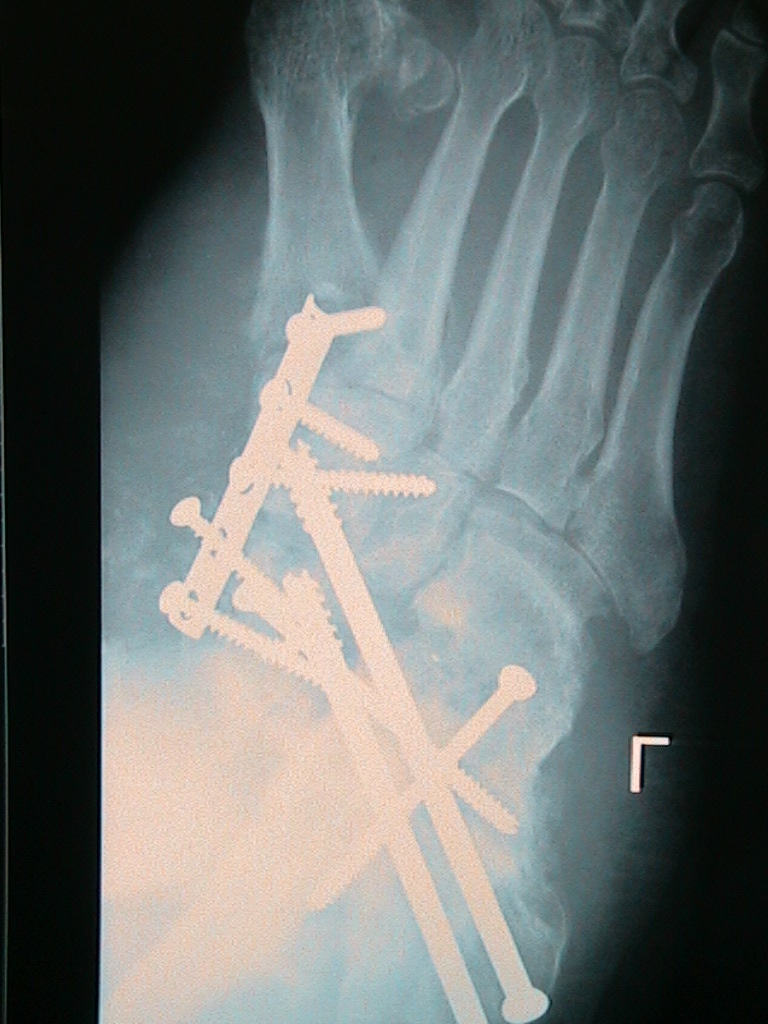

Upon further examination, it was determined that many of the sterile blisters were being caused by the implanted hardware backing out of their intended position (Figures 3 and 4). The patient was taken to the operating room, where all of his surgical hardware was removed. The patient was placed in a sterile dressing and invited back for follow-up to the clinic 3 days post-operation.

Figure 3.

Figure 4.